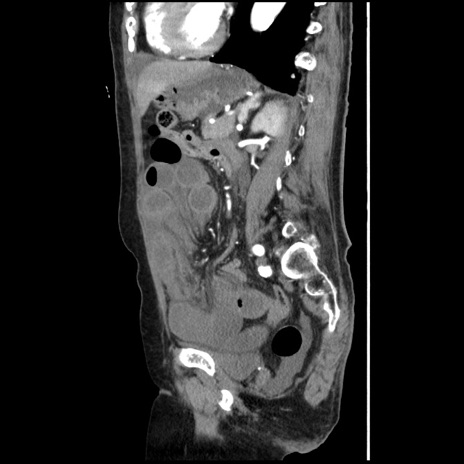

症例1(矢状断像)

【症例】80歳代女性

【主訴】腹痛

【現病歴】8時間前から腹痛あり来院。

【既往歴】糖尿病、脂質異常症、子宮体癌にて子宮全摘術

【身体所見】意識清明・会話良好だが腹痛で苦悶様、全腹部にわたって反跳痛と圧痛あり

【データ】WBC 13600、CRP 0.14、LDH 224、CK 90